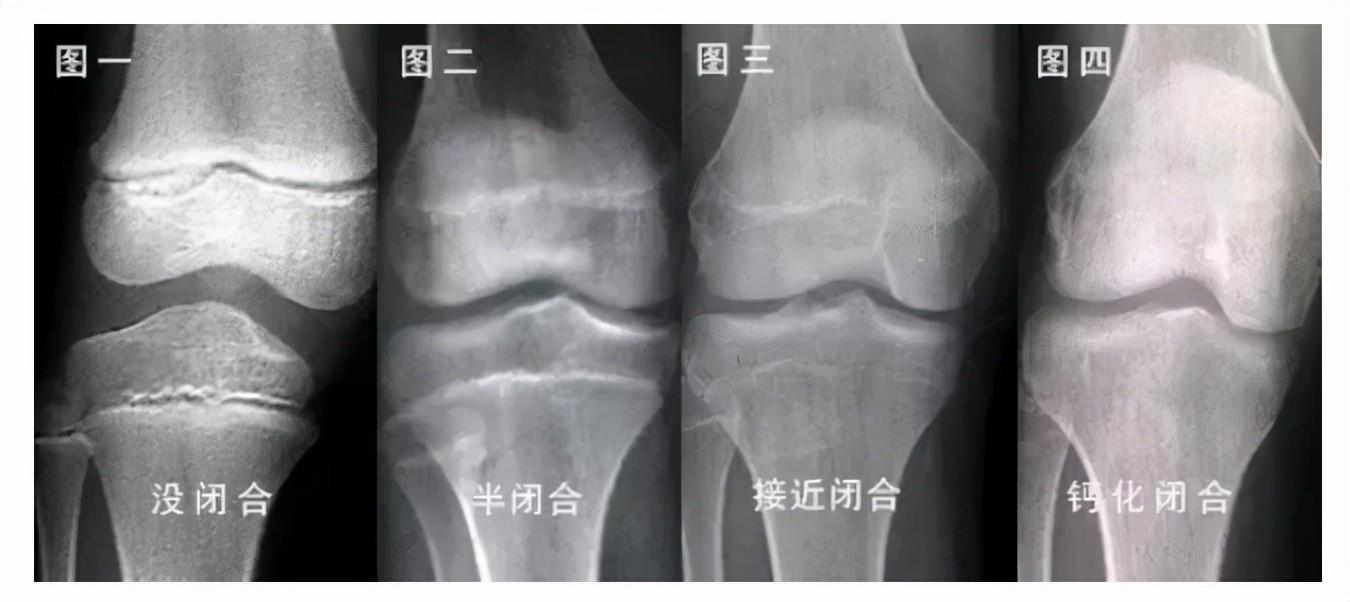

下肢的长度由大腿和小腿的「长骨」决定,长骨由软骨骨化、变成坚硬的骨质而形成。软骨位于骨骺与骨干之间。在长骨成熟前,骨骺不断向着骨干生长和骨化,使长骨不断加长。这就意味着,主要骨骺不闭合,长骨就会持续变长。

当长骨成熟后,骺板就会发现自己无需再继续骨化了,就会活动停止,形成骨骺闭合。此时,再怎么努力,长高的希望也非常渺茫了。

所以不管是小孩还是成年人,想知道自己还能不能长高,去医院拍摄X 光片,查看骨骺是否闭合。

图源:网络